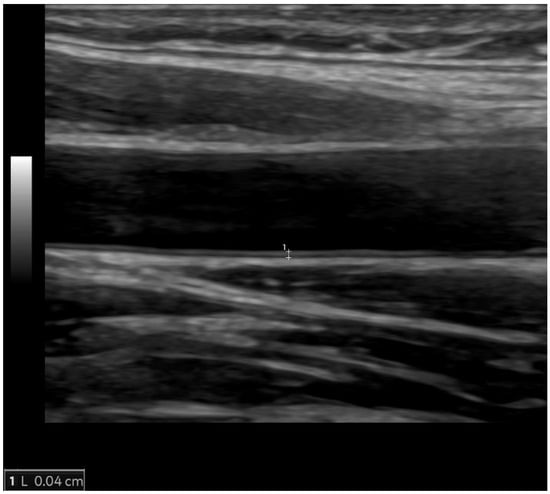

Figure 3.

The normal value of carotid intima-media thickness of 0.4 mm (between the calipers) in a young male individual.